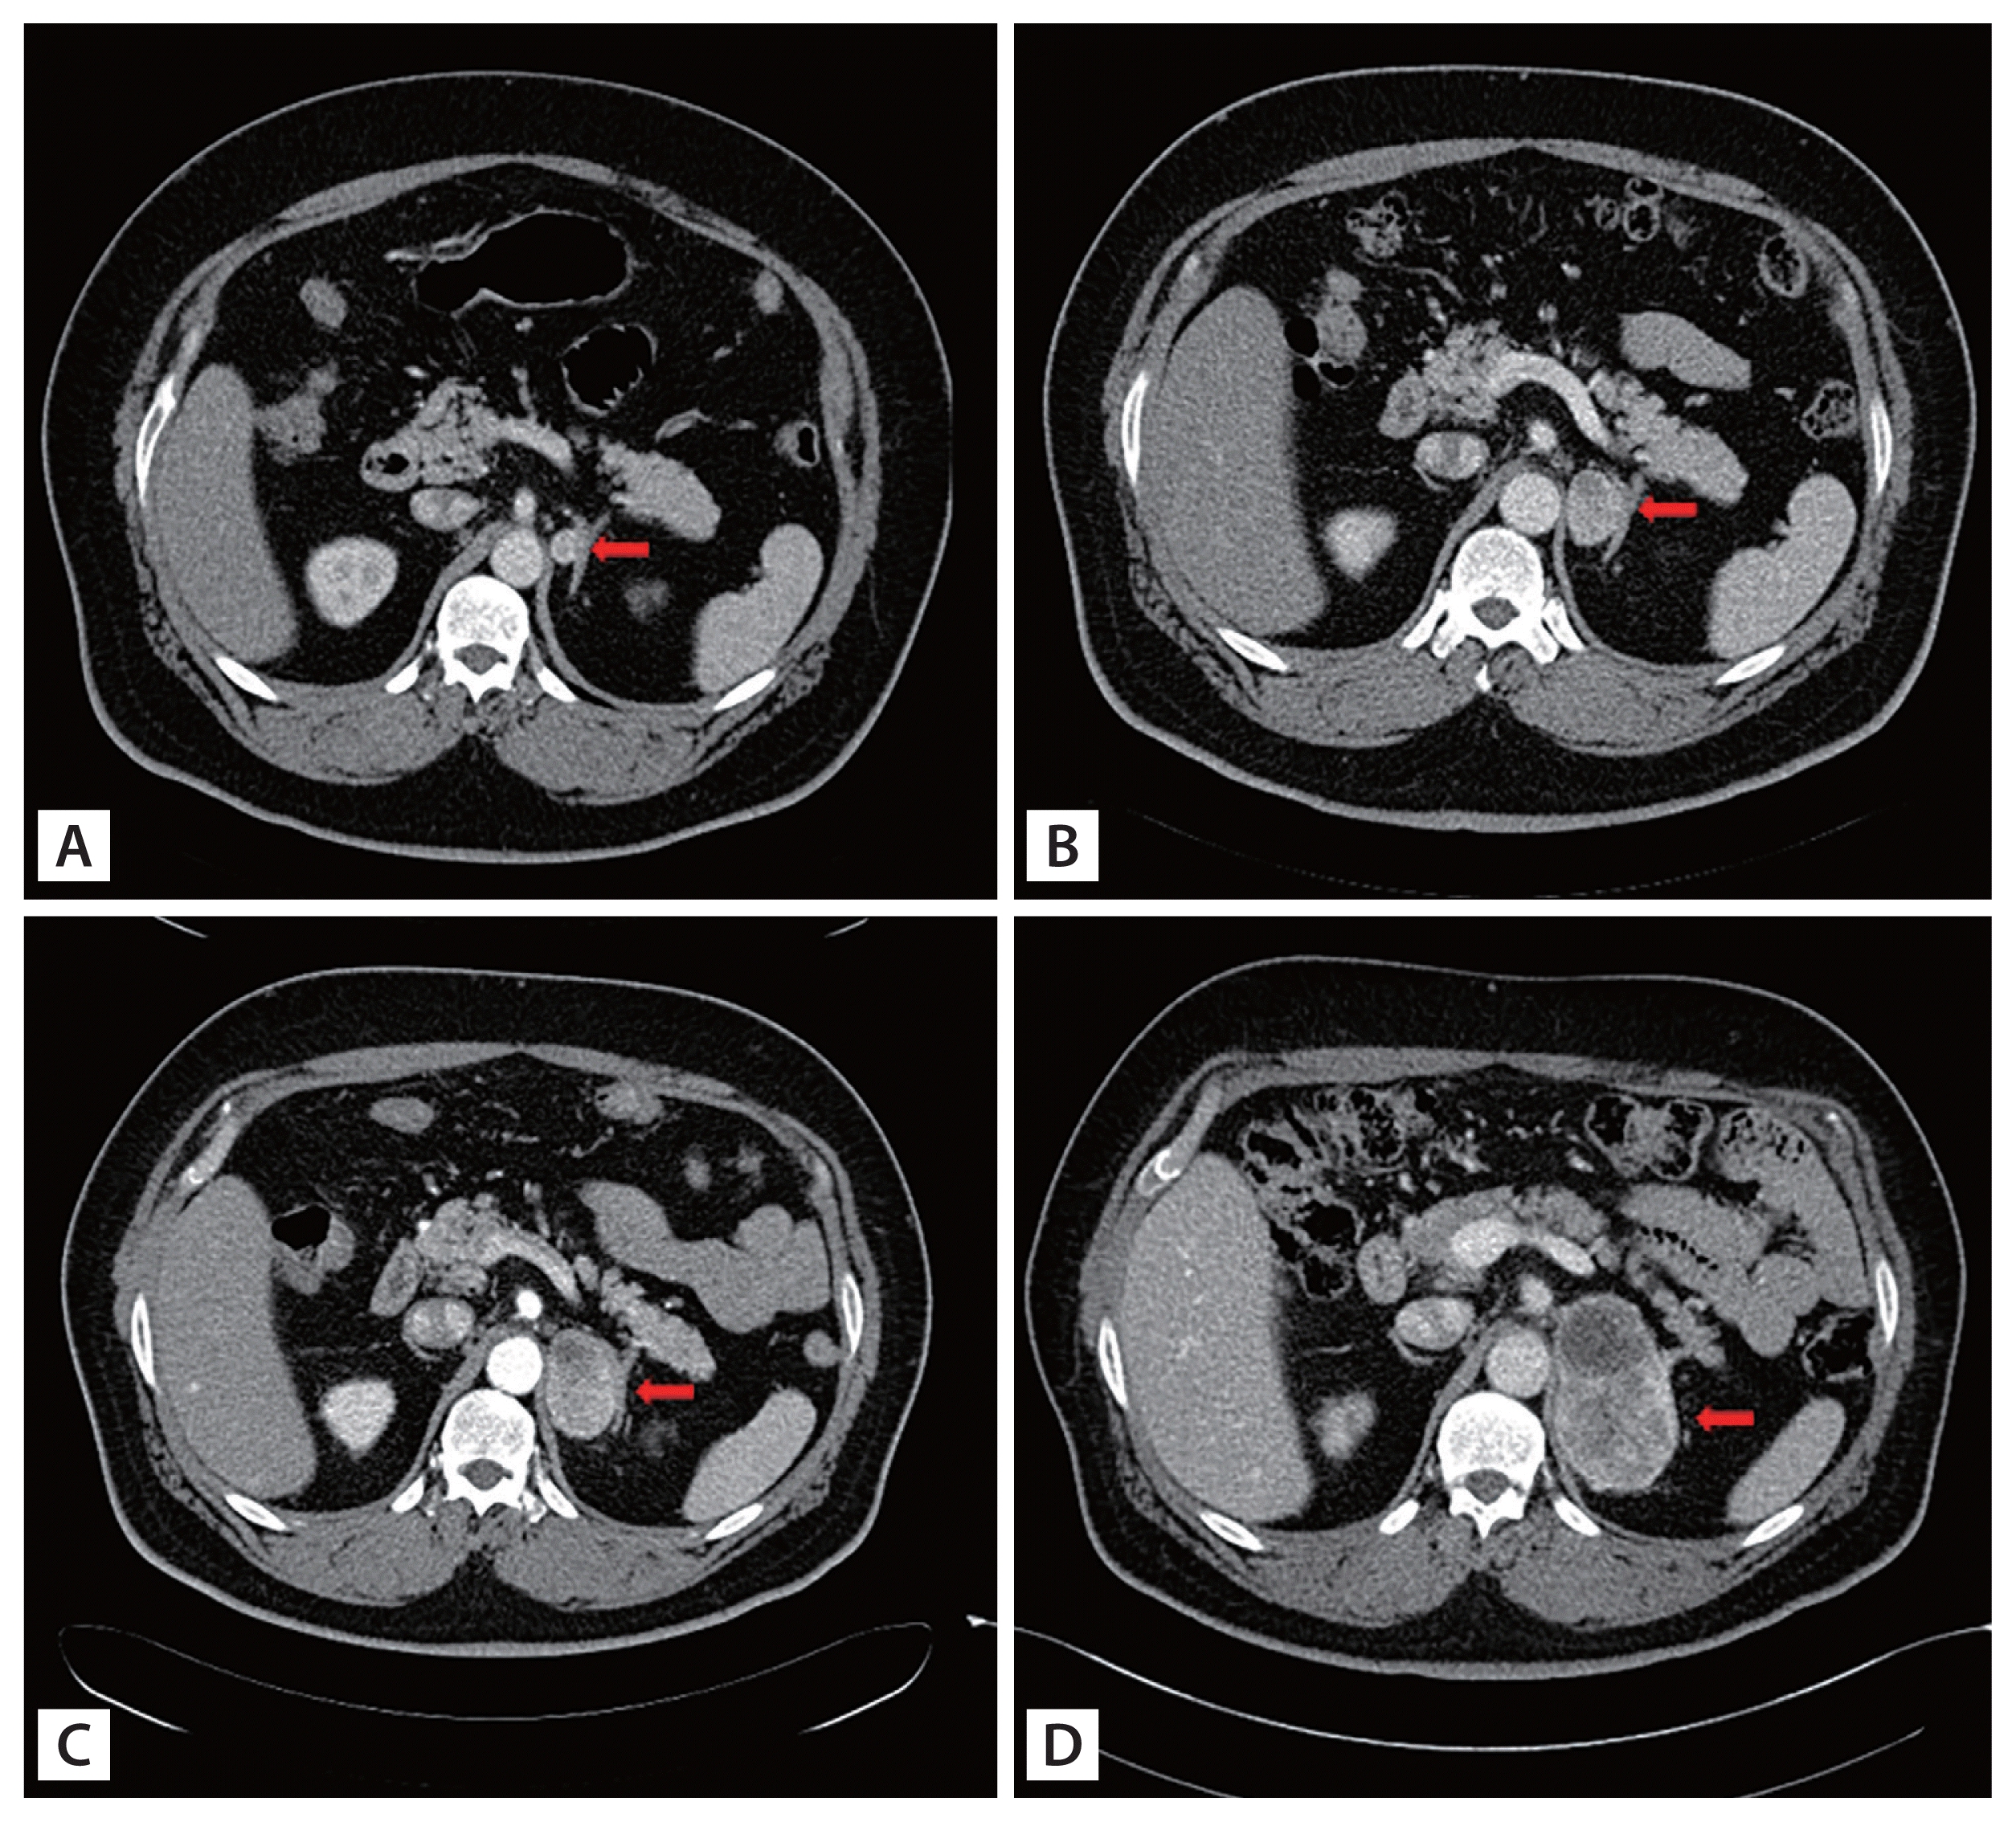

A 48-year-old man presented to our endocrinology department for the evaluation of the left adrenal incidentaloma discovered during fatty liver assessment. Abdominal computed tomography revealed a 1.8 cm left adrenal incidentaloma (Hounsfield units 40). The results of laboratory findings were as follows: serum adrenocorticotropic hormone 54.3 pg/mL, cortisol 6.39 μg/dL, renin activity 0.41 ng/mL/hr, aldosterone 12.8 ng/dL, thyroid-stimulating hormone 4.86 mIU/L, and free thyroxine 1.30 ng/dL. The 24-hour urine collection results were as follows: epinephrine 12.82 μg/day, norepinephrine 43.71 μg/day, vanillyl mandelic acid 3.10 mg/day, cortisol 39.3 μg/day. The tumor I-131 metaiodobenzylguanidine (MIBG) scan showed no abnormal uptake. The patient was diagnosed with nonfunctioning adrenal incidentaloma, and was recommended for regular follow-up. The adrenal mass continuously increased from 1.8 cm in size at baseline to 2.7 × 2.3 cm at month 15, and finally to 8.0 × 4.3 cm after 6 years of follow-up suggesting a high possibility of malignancy (Fig. 1). No hormonal change was observed during follow-up. However, the patient refused surgical management several times for personal reasons. At last, after 6 years of follow-up, he received the surgery. The pathology revealed adrenal cortical carcinoma (ACC) with 4–5/10 high-power field (HPF) mitotic rate (Fig. 2). After surgery, the patient went through several systemic chemotherapy but expired due to recurrent multiple ACC metastasis.

Figure 1

Contrast abdominal computed tomography scan shows the increasing course of a left adrenal mass (adrenal mass; red arrows). (A) Baseline 0 month, size of 1.8 cm in diameter; (B) 15 months, size of 2.7 × 2.3 cm; (C) 39 months, size of 4.7 × 3.3 cm; (D) 74 months, size of 8.0 × 4.3 cm.